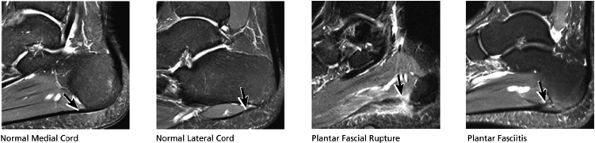

FIGURE 5.38 Plantar Fascia.

|

-

A medial segment inferior to the abductor hallucis muscle

A central segment, which originates from the medial process of the calcaneal tuberosity

A lateral segment, which originates along the lateral aspect of the calcaneal tuberosity